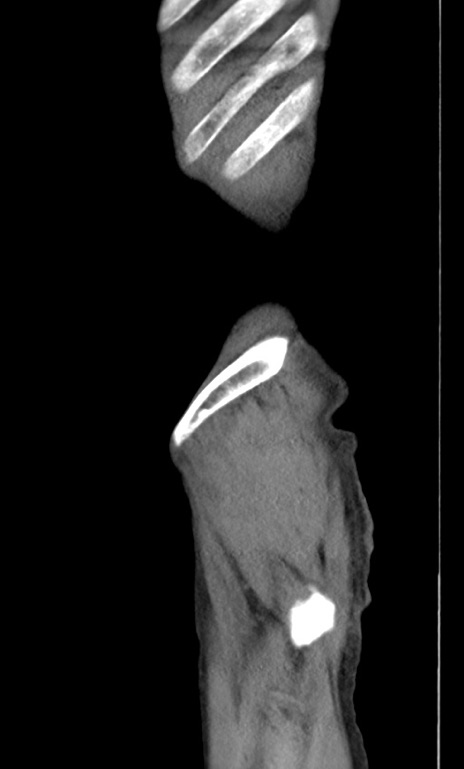

症例3(矢状断像)

横断像